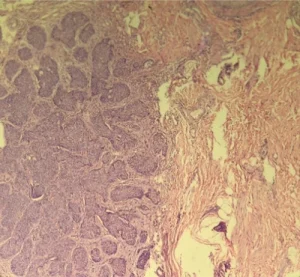

برای تأیید تشخیص، بیوپسی برشی (incisional biopsy) از ضایعه انجام شد. پاتولوژی ضایعه نشان داد:

تکثیر نئوپلاستیک درم از سلولهای اپیتلیال کوچک

نسبت بالای هسته به سیتوپلاسم

تشکیل دستههای نامنظم با پالیسادینگ سلولها در محیط (شکل ۲)

شکل ۲ — مقطع بافتشناسی نشاندهنده تکثیر نئوپلاستیک سلولهای اپیتلیال کوچک با نسبت هسته به سیتوپلاسم بالا و پالیسادینگ محیطی، به نفع BCC